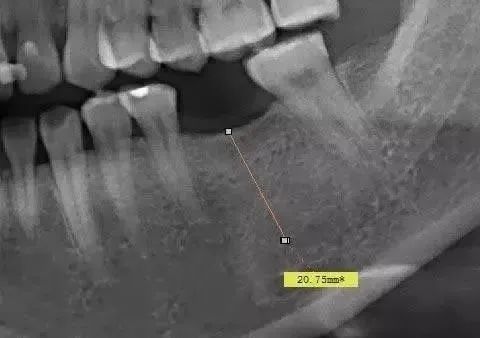

患者的下颌有一颗牙齿缺失,需要进行种植牙手术,手术前对患者的口腔进行了全景片的拍摄。并从软件中测量患者缺失牙位的可用骨高度为20.75mm。看到这个数值,如果是有经验的种植医生肯定会第一时间怀疑机器的放大率,因为通常牙齿缺失后,牙槽骨都会吸收,而尤其是牙齿缺失比较久的患者,牙槽骨的条件都不是很理想。可以说能够拥有20.75mm这么高的牙槽骨几乎是不现实的。

这个病例,如果种植医生没有很多的临床经验,直接按照全景片上测量的数据进行种植体植入的话,那么就很有可能触碰到下颌神经管。